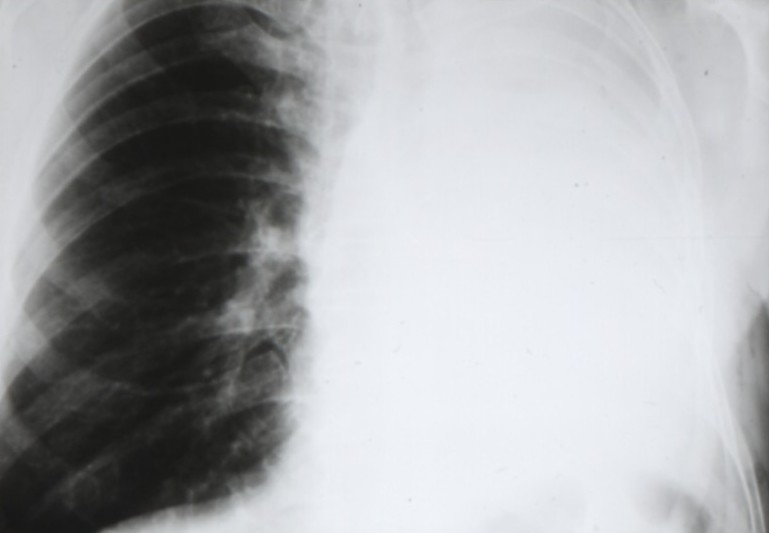

Cancers bronchiques